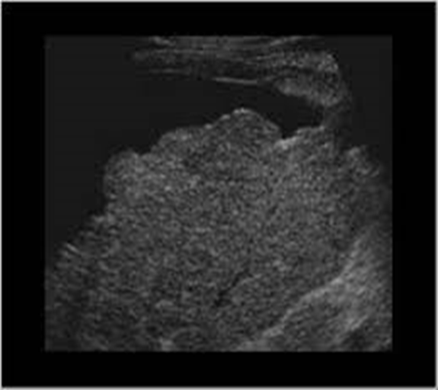

inspection of liver surface with what kind of probe demonstrates nodularity

high frequency, linear array

caudate lobe hypertrophy

nodular liver surface from cirrhosis